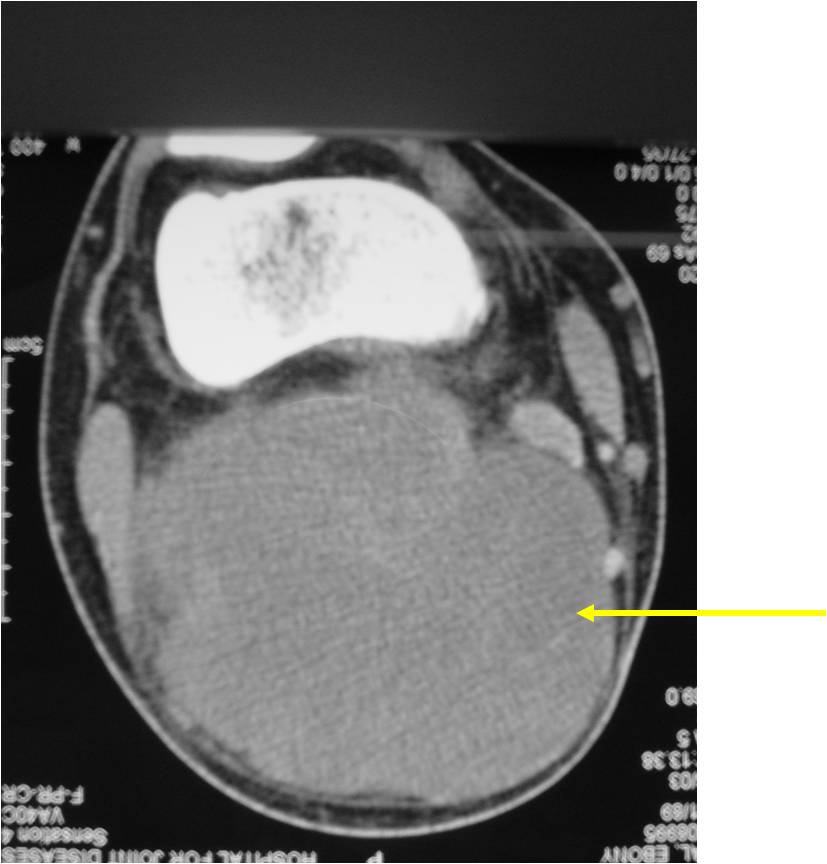

- Aggressive motheaten to permeative lesion

- Indistinct border in most cases

- Osseous destruction with a soft tissue component

- Chondroid matrix calcification may be present (60-70% of cases)

- Soft tissue mass

(Right Arrow) Cartilaginous Component